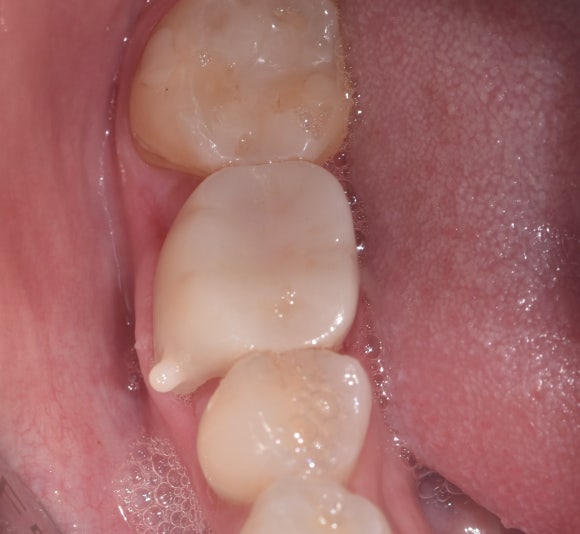

그럼 처음부터 신경치료를 할 걸 그랬네요??

라고 생각하실 수 있지만,

신경치료의 시기를 수 년 늦췄다는 점에서

이미 이전의 치료는 그 역할을 제대로 수행했다고 볼 수 있습니다.

저 또한 이러한 진료 철학을 바탕으로

환자분들께 설명드립니다.

신경치료 완료 후

머리 부분을 일차로 충전해놓은 상태입니다.

이 다음에

치아 머리를 더 정교하게 다듬어서

크라운을 씌워줍니다.

치아와 충전재 사이의 틈이 발생하지 않는 것이

장기적인 성공을 위해 중요합니다.